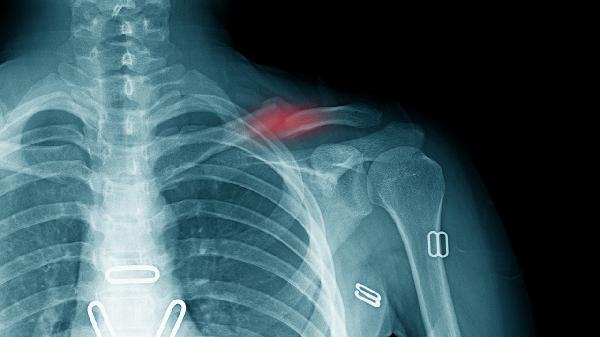

锁骨骨折通常采用八字绷带或锁骨带固定,严重移位需手术钢板内固定。钙片无法替代物理固定,但可为骨痂形成提供原料。固定期间需定期复查X线观察对位情况。